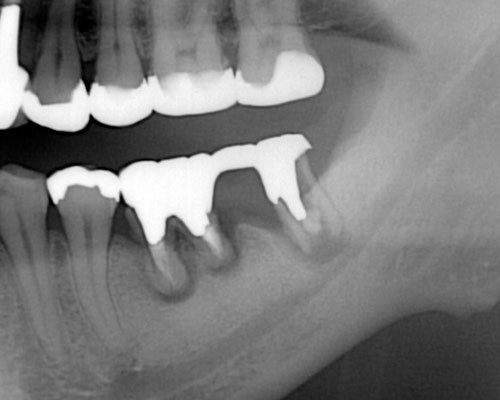

歯の根が割れた 歯の根が割れた場合、初期症状は亀裂が入った時と同じで、歯ぐきが腫れたり、噛むと痛いといった症状が出ますが、しばらくすると、あまり痛みを感じなくなります。歯の根が完全に割れてしまうと、割れ目に沿って骨はなくなりますが、膿みが出やすい状態となるため、むしろ痛みは軽くなります。歯が割れていることに気づかない方も多く、レントゲンを撮って初めて気付く方も多いのが特徴です。